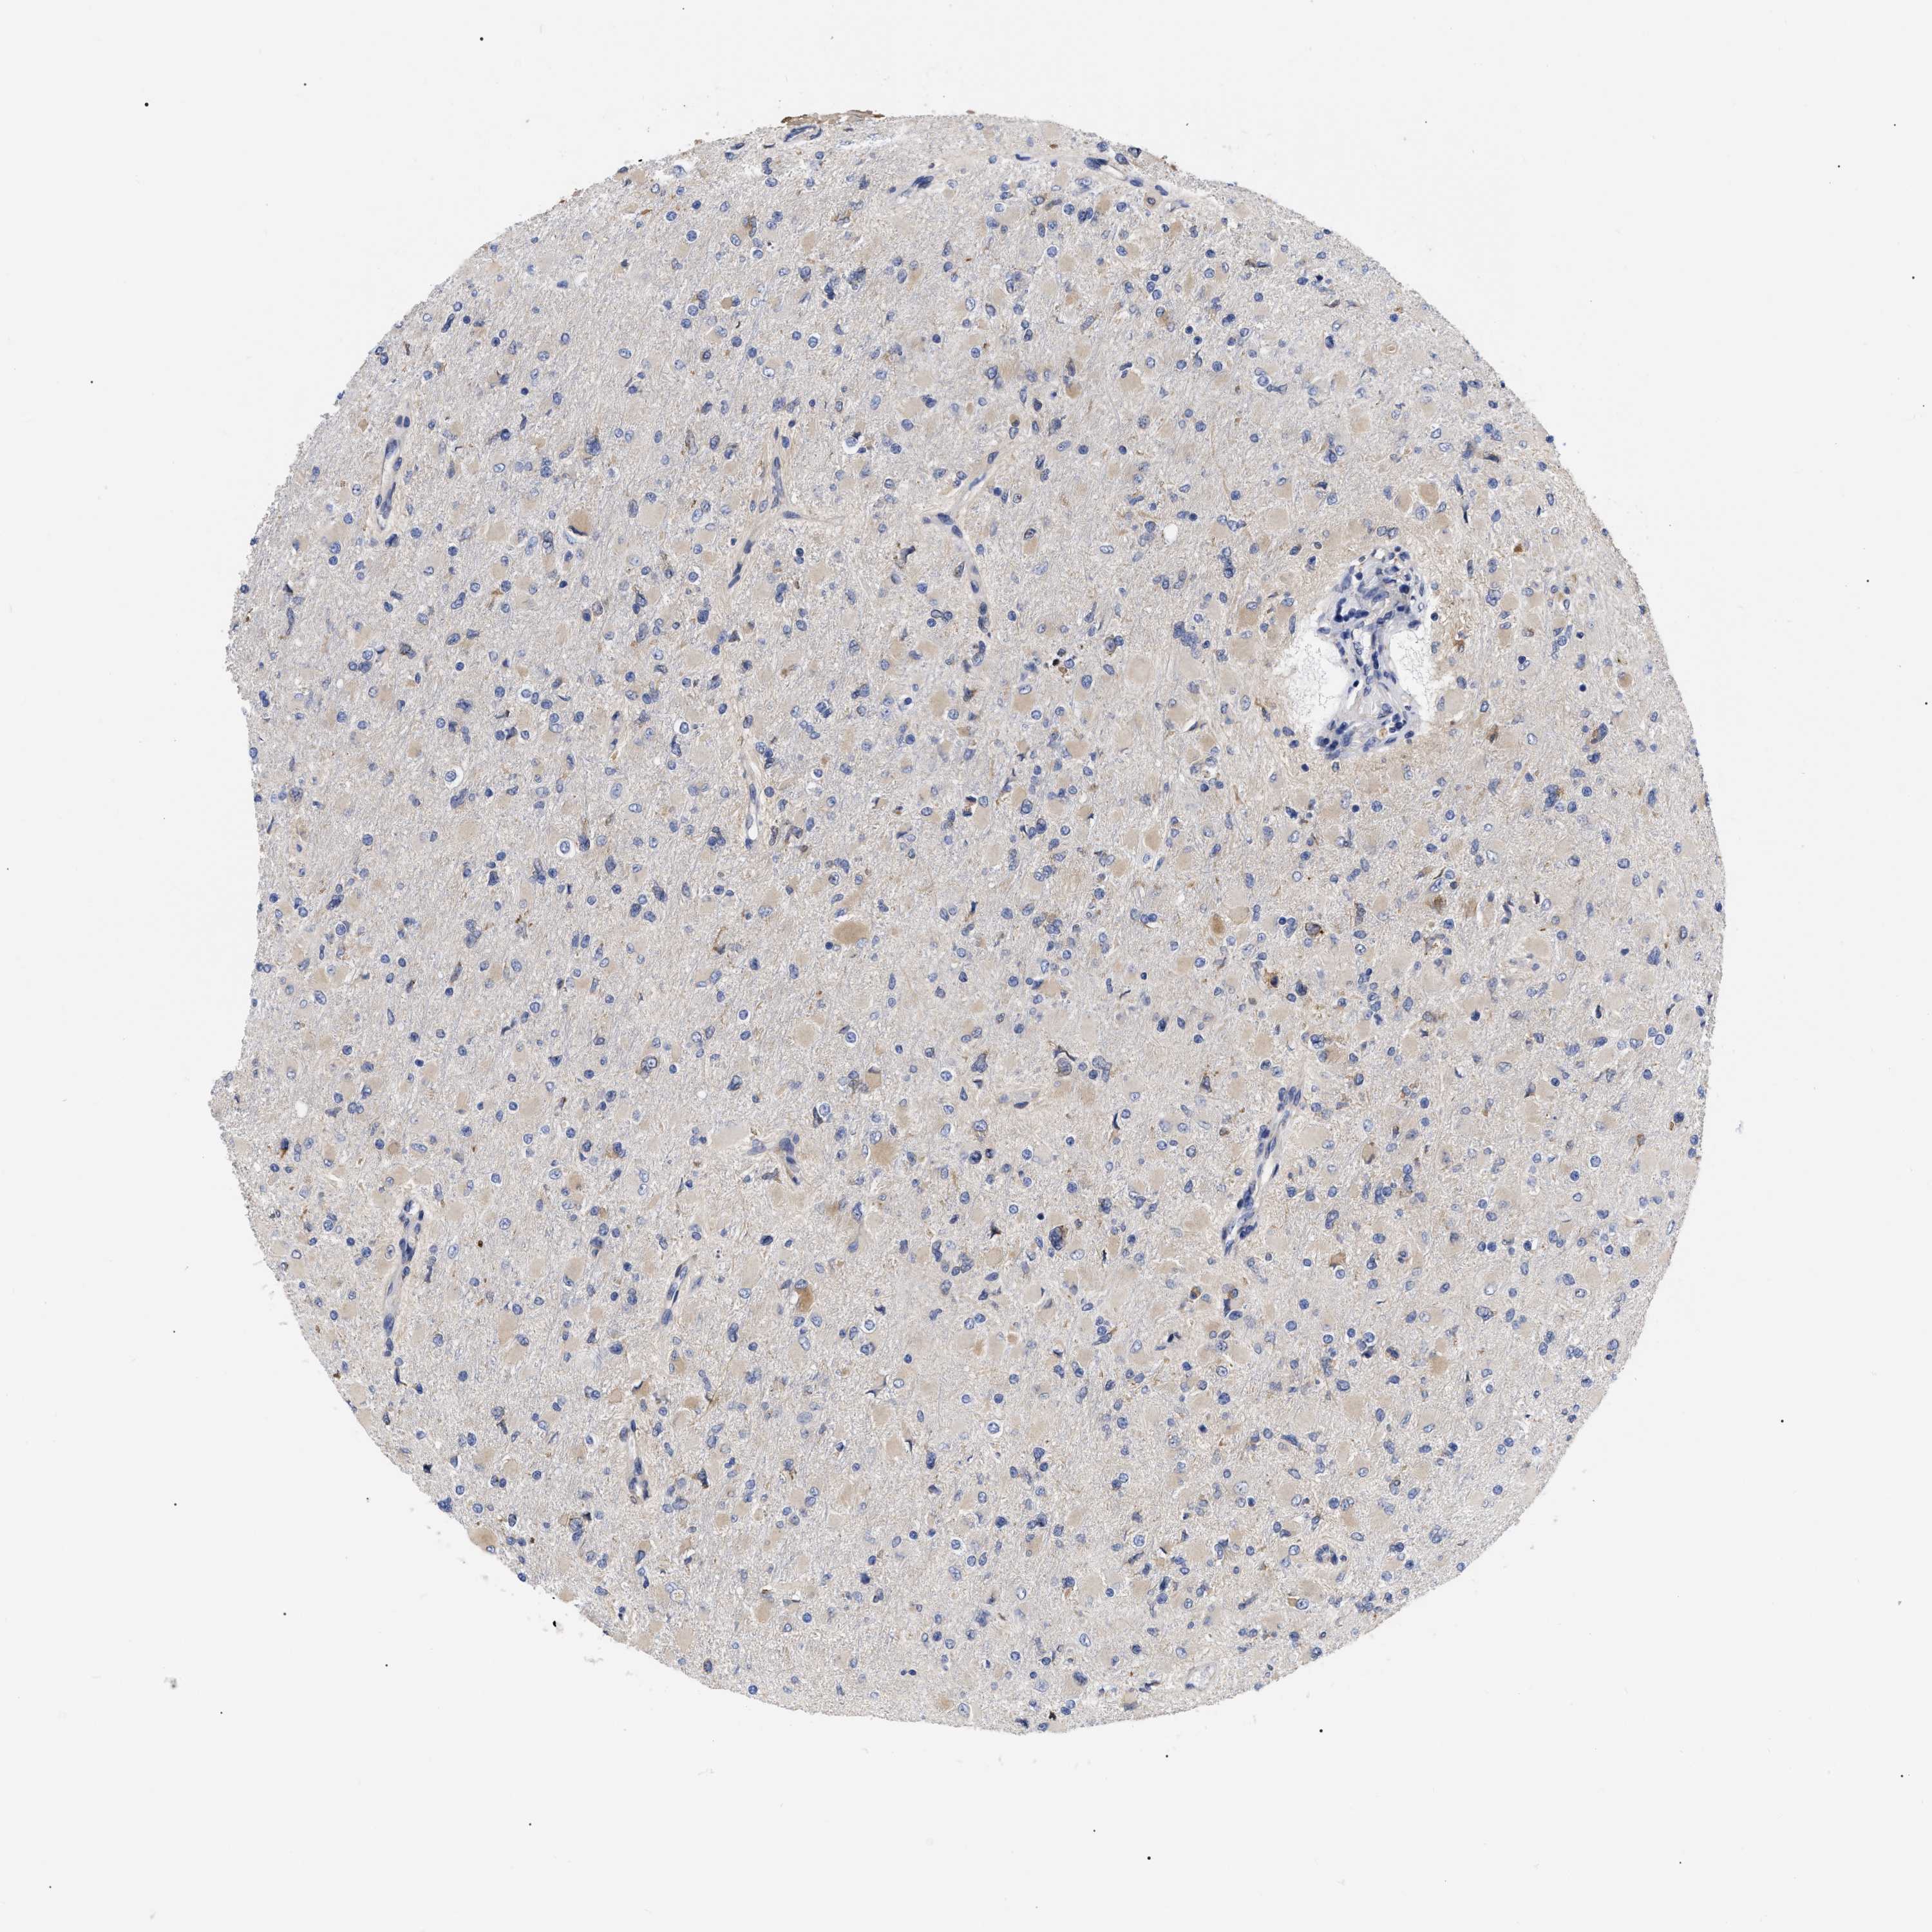

GLIOMA - Protein expressioni

A mouse-over function shows sample information and annotation data. Click on an image to view it in a full screen mode. Samples can be filtered based on level of antibody staining by selecting one or several of the following categories: high, medium, low and not detected. The assay and annotation is described here.

Note that samples used for immunohistochemistry by the Human Protein Atlas do not correspond to samples in the TCGA dataset.

Antibody stainingi

Antibody staining in the annotated cell types in the current human tissue is reported as not detected, low, medium, or high, based on conventional immunohistochemistry profiling in selected tissues. This score is based on the combination of the staining intensity and fraction of stained cells.

Each image is clickable and will lead to virtual microscopy that enables deeper exploration of all samples and also displays staining intensity scores, fraction scores and subcellular localization as well as patient and tissue information for each sample.

Antibody HPA018453

Antibody HPA019055

Antibody HPA028849

Antibody CAB034170

Glioma, malignant, High grade

Glioma, malignant, Low grade

Glioblastoma, NOS